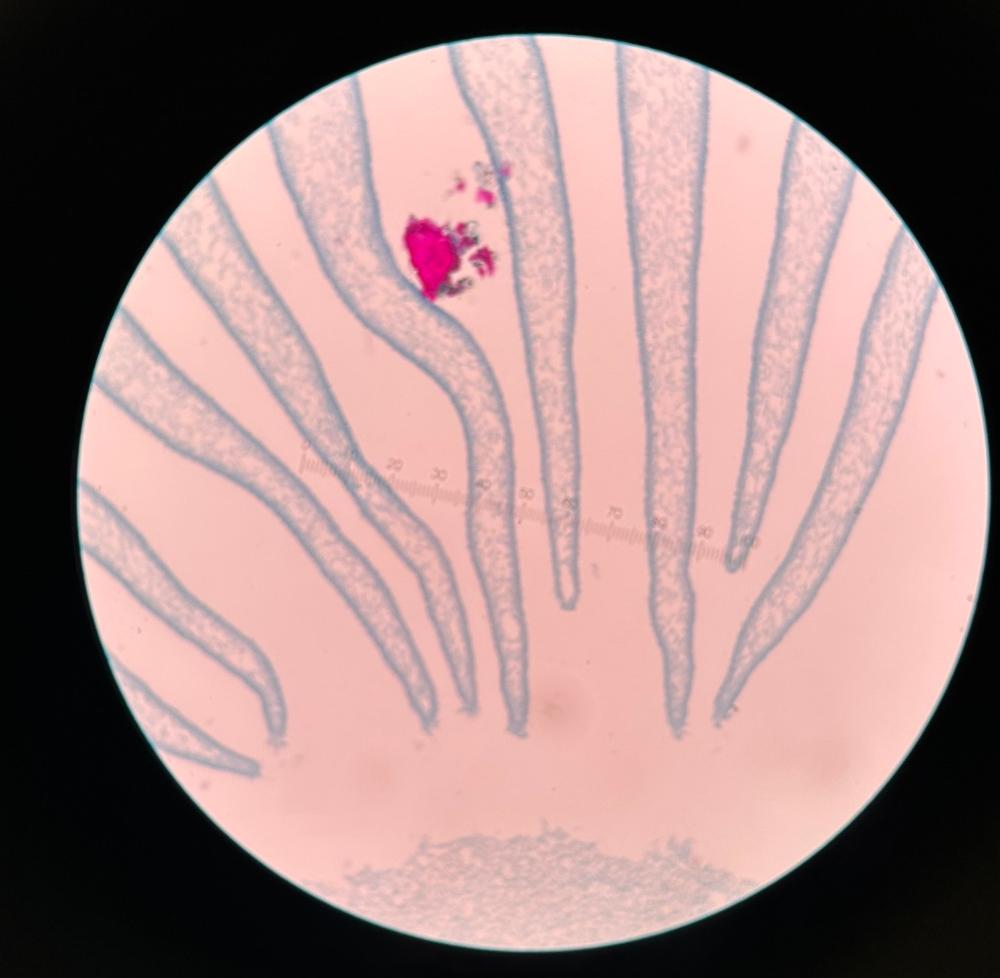

Trichinella (male & female)

Trichinella (muscle section)